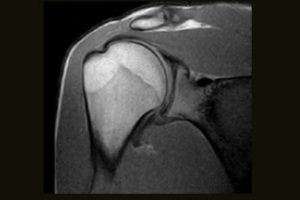

Clinical Images

Immediate access to high quality MR images can help your practice achieve new levels of efficiency and patient satisfaction. From C-spine anomalies to foot injuries, the S-scan dedicated MRI system efficiently delivers a range of MSK MRI studies within your existing practice.

Comprehensive MSK Imaging